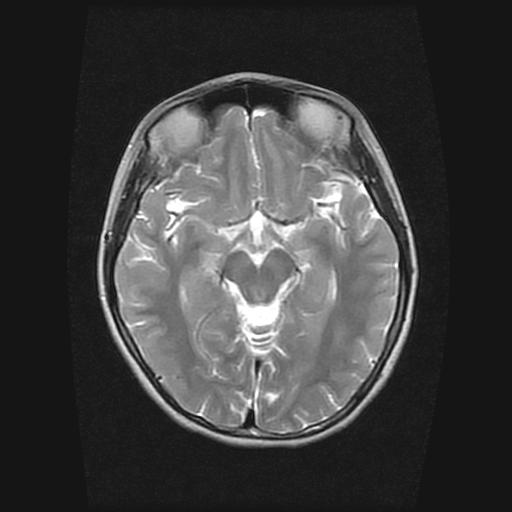

9岁女孩,三岁时诊断为癫痫,一直服丙戊酸钠,现患者一般情况良好,家长复查核磁片,看能否停药..

巨脑回

未见异常信号灶.

停药要结合临床,如无发作可以停。